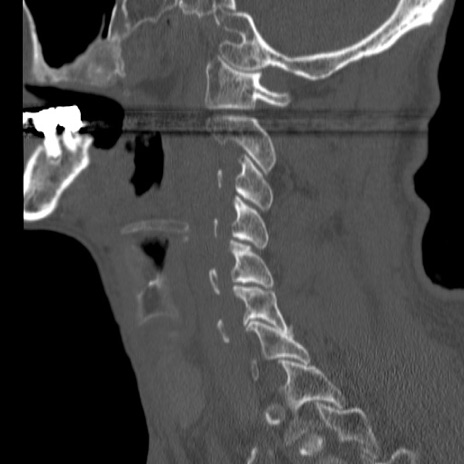

症例46 頚椎CT(矢状断像)

【症例】80歳代男性

【主訴】両側頚部〜上肢のしびれ

【現病歴】昨日、自宅内で転倒、その後より上記症状あり。意識障害なし。

【身体所見】両側上肢のallodynia(熱痛覚過敏)あり。MMTおよびDTRは正確な所見取れず。両上肢の挙上はなんとか可能。

異常所見と診断は?